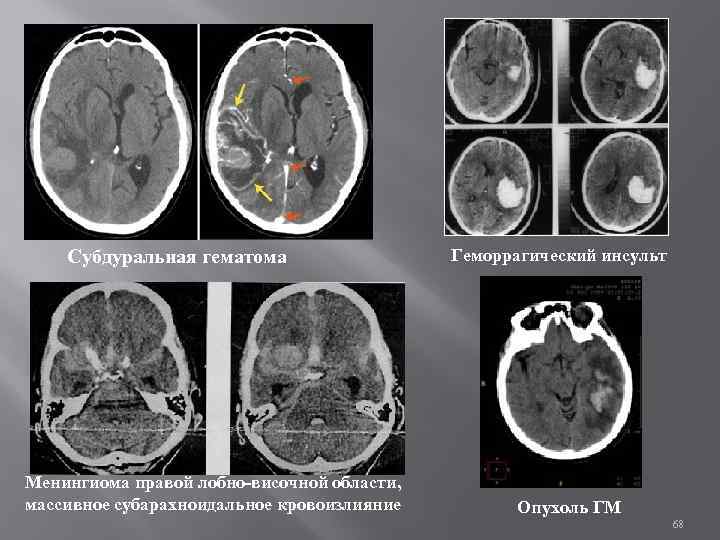

Субдуральная гематома Менингиома правой лобно-височной области, массивное субарахноидальное кровоизлияние Геморрагический инсульт Опухоль ГМ 68